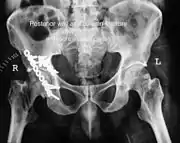

To understand the fracture pattern of a fractured acetabulum, it is essential to have minimum three x-ray views, though use of CT scan with 3-D reconstruction of images has made understanding of these fractures easier.

- Pelvis with both hips antero posterior view. This view shows six important landmarks of the acetabulum, specifically:

- Pelvic brim

- Ilio ischial line

- Tear drop

- Anterior wall

- Posterior wall

- Weight bearing dome